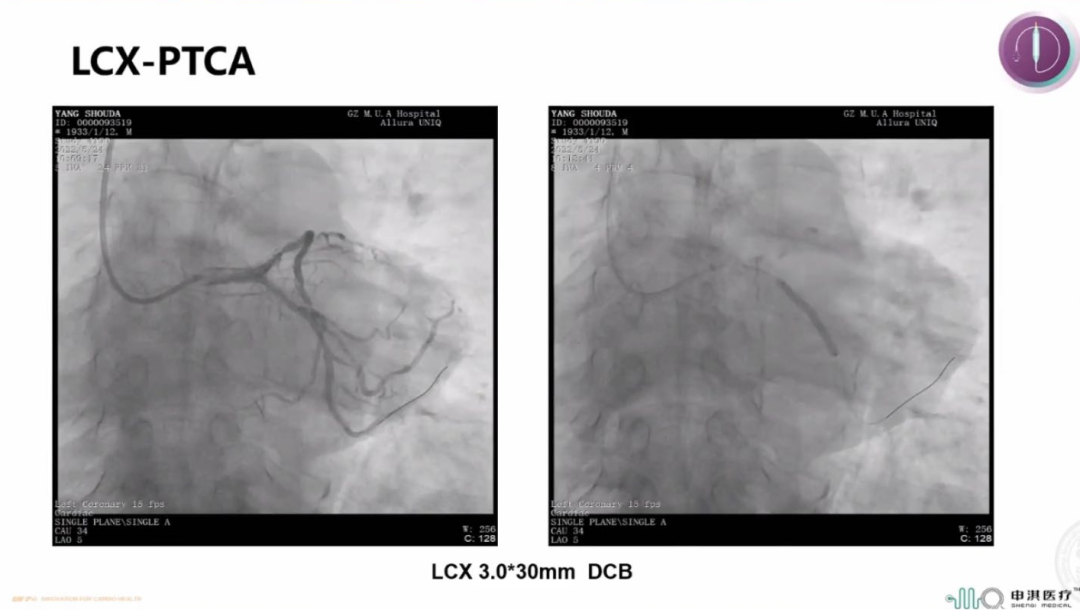

该患者为90岁高龄男性,既往有PCI史,且合并糖尿病、高血压、慢性肾功能不全。冠脉造影示LCX支架内次全闭塞,合并重度钙化;LAD近中段弥漫狭窄。手术过程中首先对LAD行IVUS检查示MSA 3.45mm²,可见表浅的钙化斑块。ISR是DCB的IA类适应症,于是术者在进行充分预处理后首先使用申淇3.0*30mm DCB扩张LCX-ISR病变80s。LAD病变弥漫,且患者为高出血风险,于是同样选择申淇3.5*20mm DCB治疗LAD病变,手术即刻效果满意。